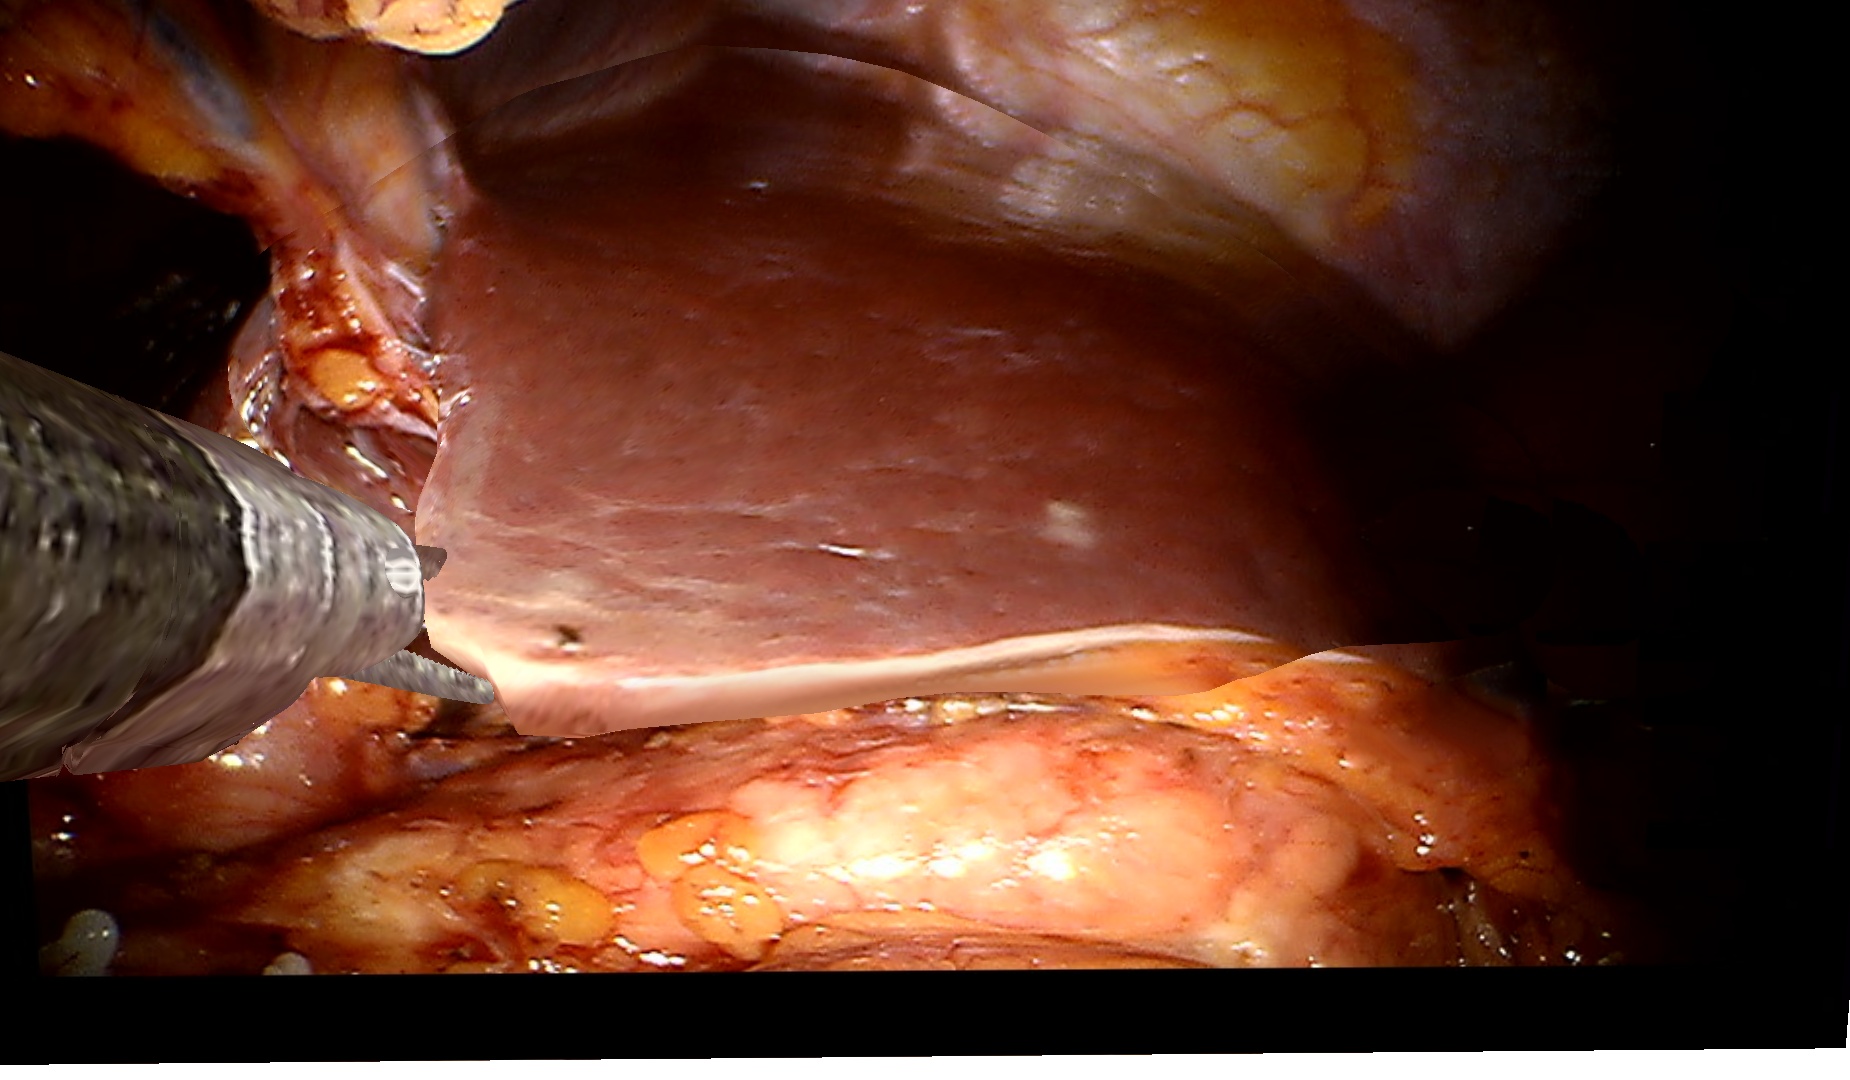

To demonstrate the effectiveness of our method on clinical data, we use a dataset of two visceral pig surgeries with a preoperative post-insufflation CT, initial rigid registration, a tracked laparoscope, and corresponding 2D monocular RGB videos. Surgical tools were masked out using SurgicalSAM [23]. The first sequence from the first surgery shows a tool-tissue interaction, whereas the second one shows a breathing motion without external manipulation. Because there is no deformed ground truth, as measuring intraoperative deformation would require intraoperative scanning, we demonstrate qualitative results.

Figure˜4 shows results on the tool-tissue interaction. The surgical tool presses down on the stomach, leading to the deformations tracked in the deformed mesh and CT (bottom rows). Although the difference in pressure applied between B and C appears marginal, we successfully track the increasing deformation, the difference being visible in both mesh and CT. For D and E, the tool is repositioned, now pulling the stomach back. Note how this backward pull is visible in the respective deformed CTs by a deformation to the right, since the laparoscope captures the scene roughly in the coronal plane, whereas the CT slice is shown in the sagittal plane.

Refer to caption

Figure 4: Examples from a tool-tissue interaction sequence. Rows from top to bottom: input images acquired by the laparoscope, images rendered with our method, deforming mesh, and deforming CT. Arrows in A point to the deforming anatomical structure, circles in B highlight the area of deformation, and arrows in E visualize the pull direction. See video in the supplementary material.

Since we rely on an initial registration, we are also subject to registration errors. There is a slight misalignment between the structure being manipulated in the input images (stomach) and the deforming mesh. Also note that we initialize our mesh from a post-insufflation CT, ensuring that the initial mesh and the intraoperative state early in surgery are still very similar. Regarding the deformation of the CT, we can only capture surface deformations by deforming our mesh. A more realistic deformation of deeper layers would require biomechanical modeling. Apart from those caveats, the method does not work in real time yet. Given the strides being made in the 3D computer vision community around 4DGS, we are confident that this problem will be solved soon. Despite those limitations, the deformations of the stomach in the CT are sensible and correspond to the tool-tissue interaction as confirmed by a board-certified surgeon.